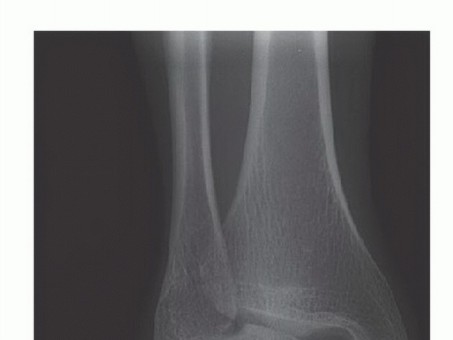

DEFINITION The term osteochondral lesion of the talus (OLT) refers to any pathology of the talar articular ca…

DEFINITION Osteochondral lesions of the talus (OLT) are common conditions that can involve both the cartilage…